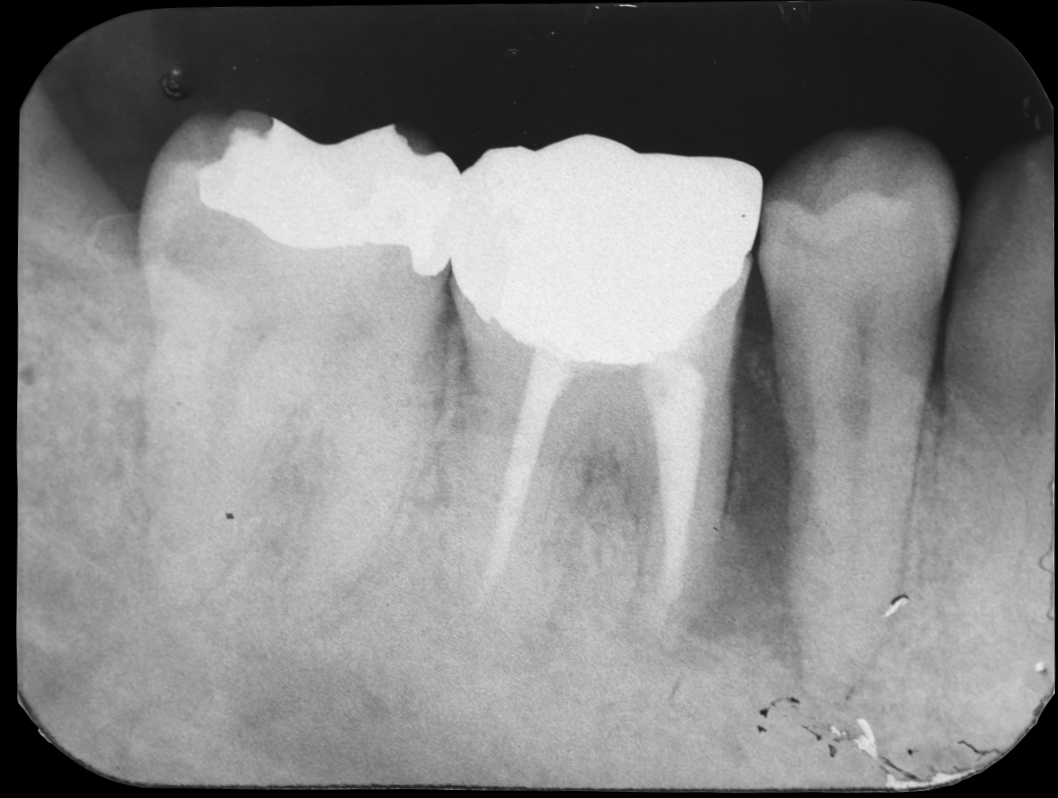

- Before

頻繁に奥歯のまわりが腫れてくるとのことでご来院されました。初診時は応急的に抗菌薬で炎症を抑えて、後日現状を詳しく精査していきました。

2本あるうちの手前の1本の根っこが縦に割れてしまっている状態でした。折れた手前の根だけ抜歯して、奥の根を残しても余分な負荷がかかって予後が良くないことは自明です。患者様との相談の結果、奥歯を抜歯してインプラント治療をしていく運びとなりました。まず周囲組織に負担がかからない方法で慎重に抜歯していきます。